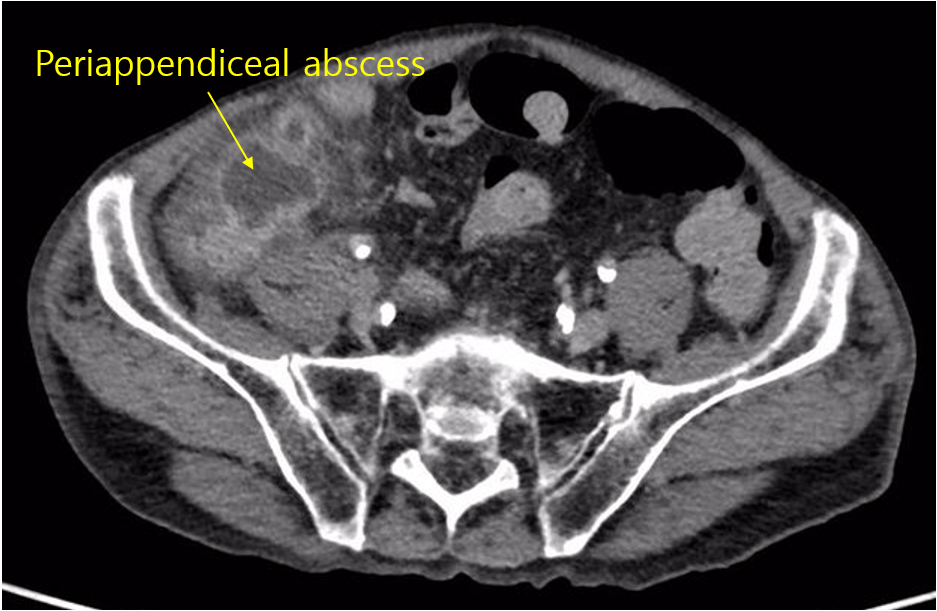

(3) Appendix 주위의 fluid collection, air (↔ appendix lumen 내부의 air는 정상 소견)

3) Complicated/perforated appendicitis: 천공의 증거가 있는 경우 (주로 수 일 ~ 수 주 동안 증상 지속)

(1) 농양 동반: 바로 수술하지 않음

① 항생제 투여 + 농양 배액(> 3cm일 경우)

② 진단 후 6~8주의 간격을 두고 interval appendectomy 시행

* Appendicitis 발병 후 오랜 시간이 지나 천공 및 농양 형성까지 이루어졌을 경우, appendix 뿐만 아니라 근처 ileum, cecum도 염증이 심한 경우가 많다. 이 경우 곧바로 수술하면 ileum/cecum을 충수돌기와 같이 절제해야 할 가능성이 높다. 따라서 우선 항생제를 투여해 염증을 가라앉힌 후, 추후 재발 방지 및 appendiceal cancer의 가능성 배제를 위해 interval appendectomy를 시행하는 것이다.